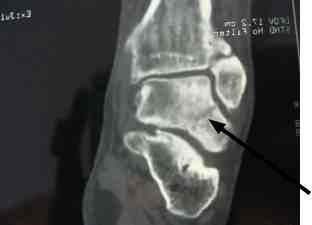

He first consulted me a year and a half later. The ankle was still swollen, and there was considerable discolouration of the skin. Eversion was severely limited.

Fractures in the ankle are notoriously difficult to see because of the overlapping structures. A scan revealed the partially healed fracture through the talus bone.

Worse, because of the disrupted blood supply to the talus, the main bone joining the leg to the foot is dying. A process called "avascular necrosis."

Can you see the great holes of dead bone in the talus? The fracture cut off the blood supply to the osteoblasts. It should have been pinned immediately.

How reliable are X-rays? Sometimes fractures can only be seen on a scan.

Whilst gentle Chiropractic mobilisation of the joints around the talus brought about 50% relief of pain and stiffness for about six months, it's proved temporary. The talus is a major weight-bearing bone. A total ankle replacement is on the cards.

Not because of the original injury, but because the missed fracture led to inappropriate treatment.